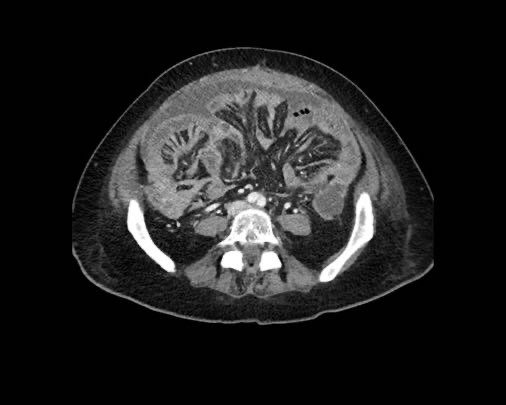

Hình ảnh

Hình ảnh CT của một bệnh nhân ung thư phúc mạc.

Một lượng nhỏ dịch cổ trướng hiện diện ở góc phần tư trước bên phải.

Các đường dày dạng nốt vuông góc với thành ruột được ghi nhận.

Hình ảnh này đại diện cho tổn thương xâm lấn mạc treo ruột lan rộng (mũi tên).